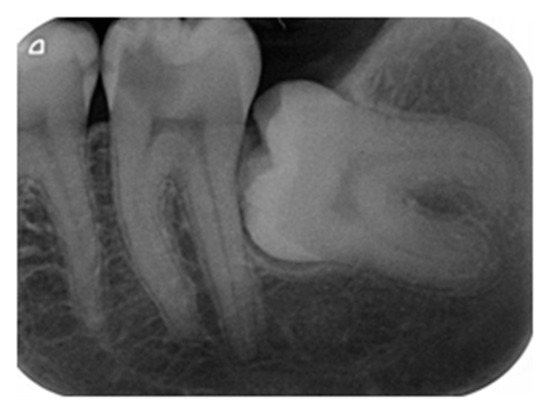

- Demant, S.; Dabelsteen, S.; Bjørndal, L. A macroscopic and histological analysis of radiographically well-defined deep and extremely deep carious lesions: Carious lesion characteristics as indicators of the level of bacterial penetration and pulp response. Int. Endod. J. 2021, 54, 319–330. [Google Scholar] [CrossRef]